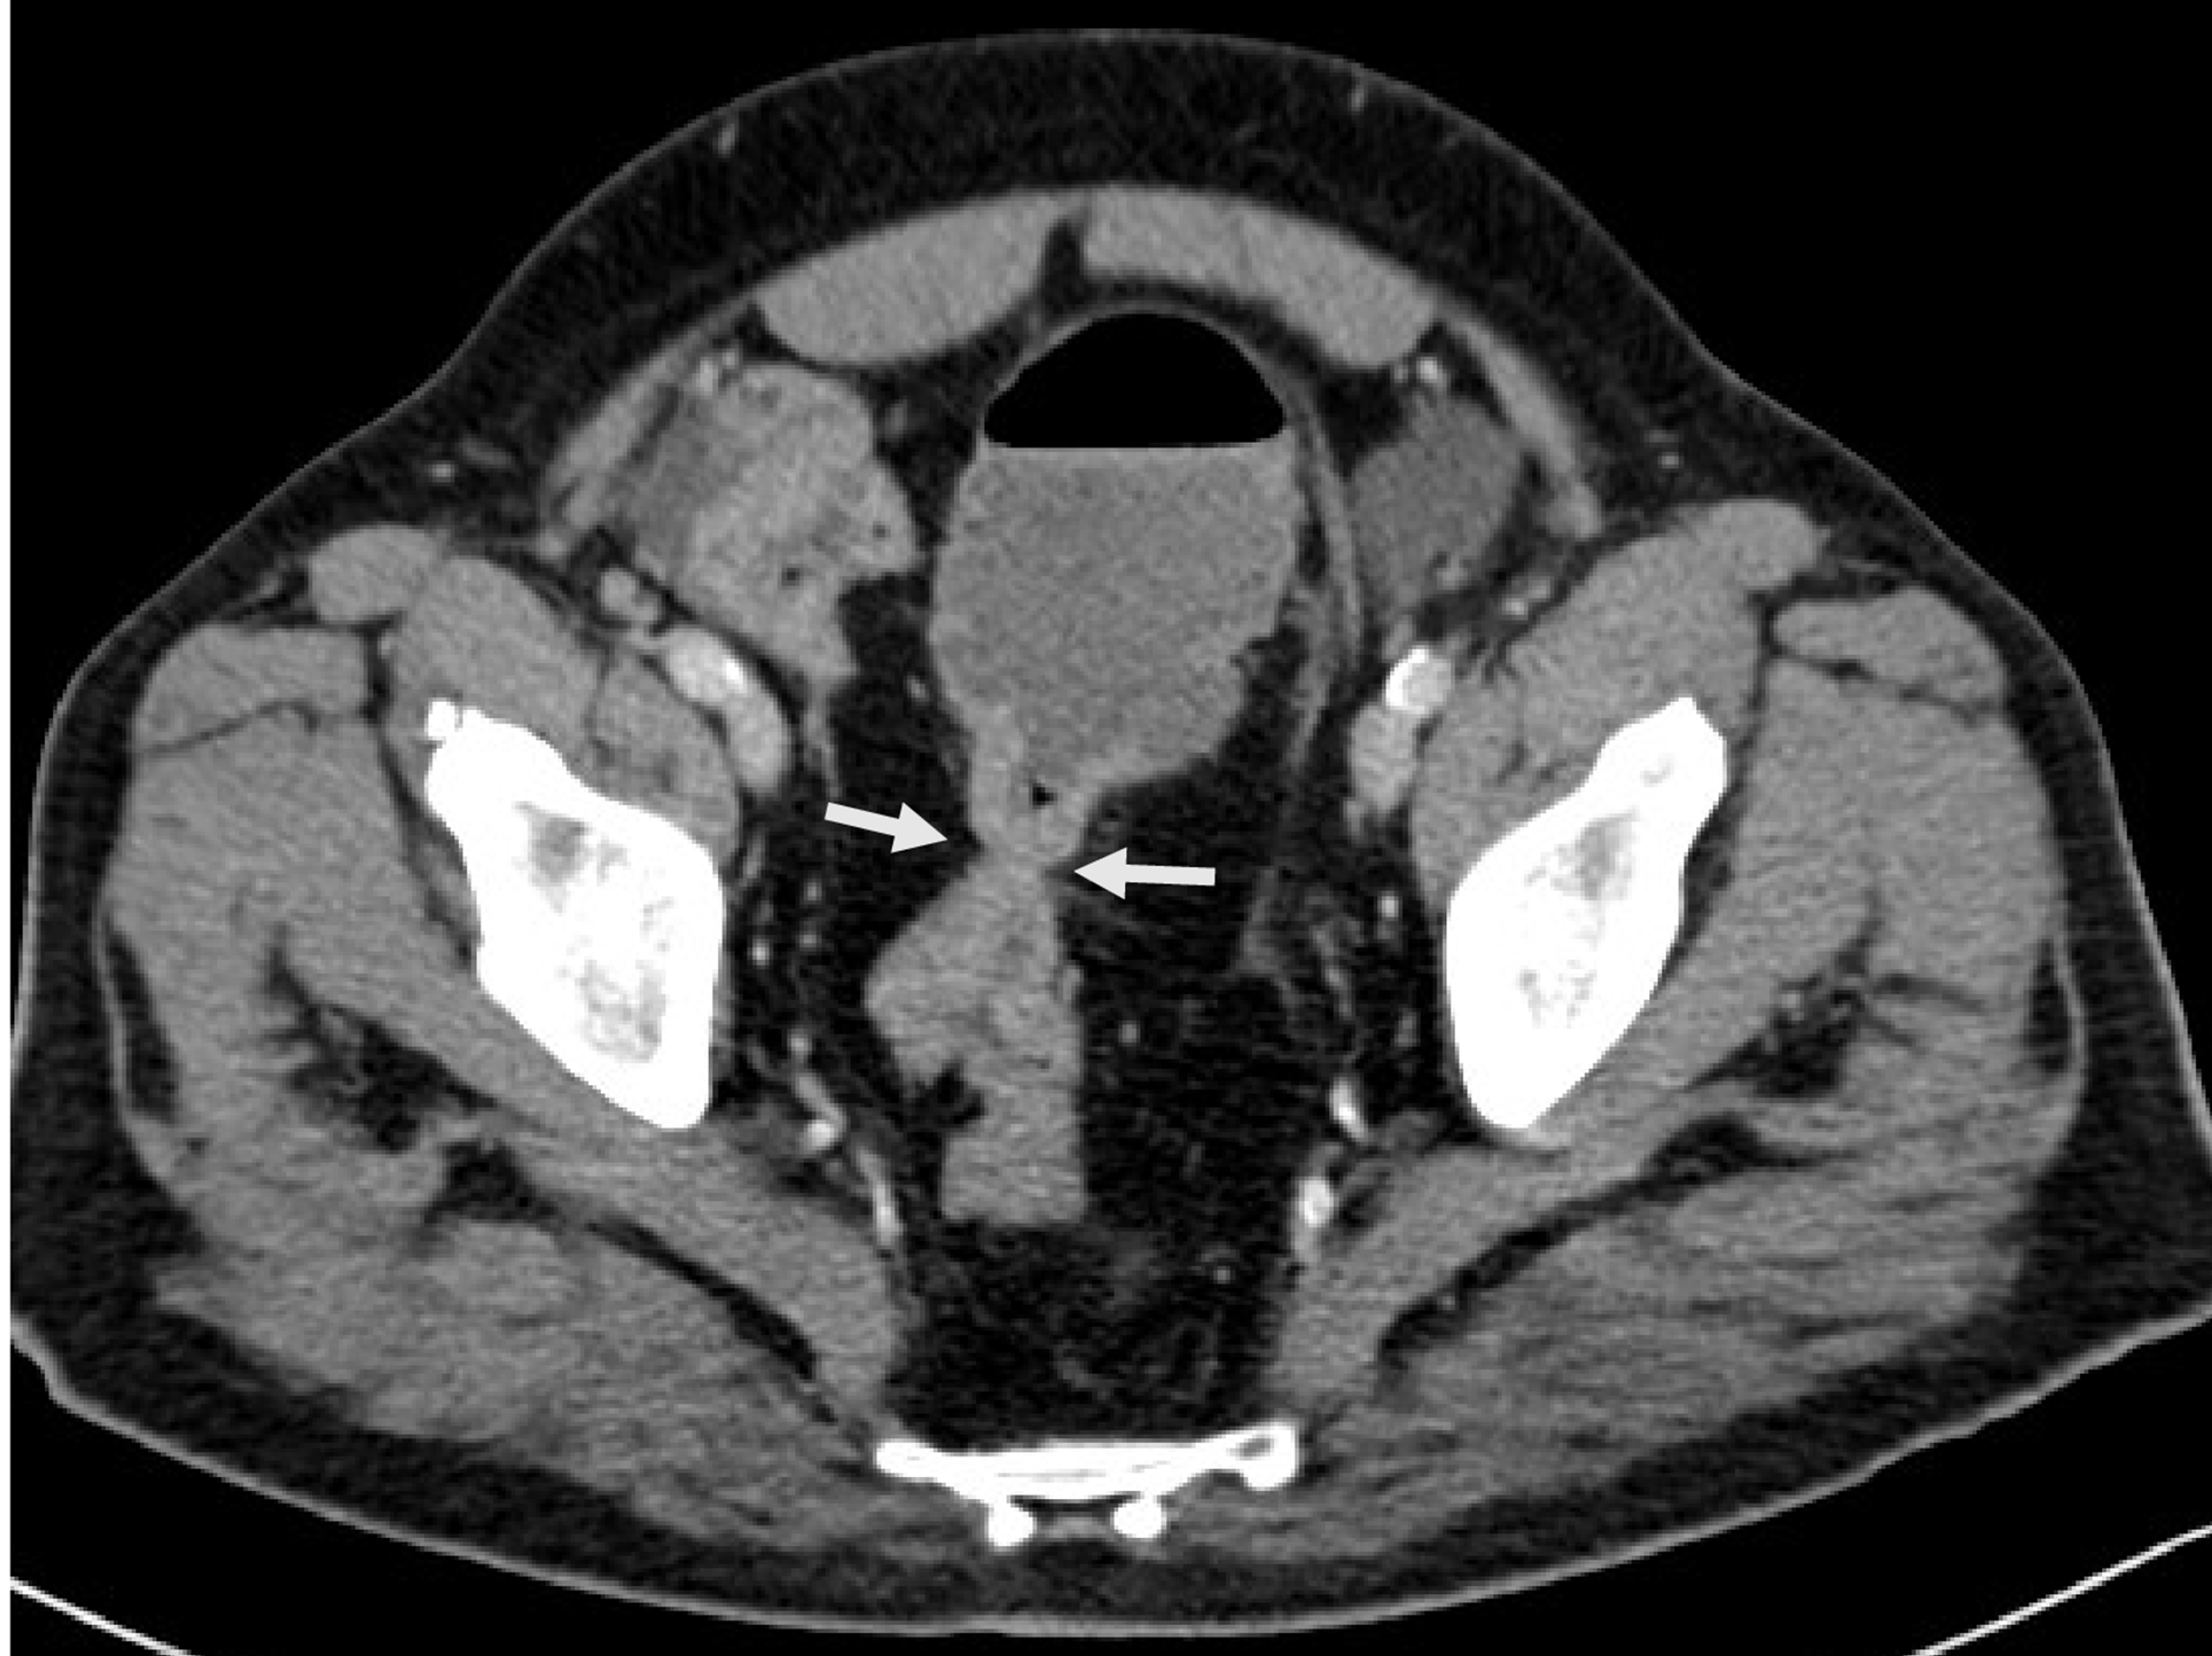

From www.thepermanentejournal.org

Pyomyositis as an Unusual Presentation of Colonic Adenocarcinoma The Permanente Journal Apple-Core Lesion Colon Cause “apple core lesions” on abdominal imaging are commonly associated with malignancy constricting the colonic lumen. the apple core sign, also known as the napkin ring sign (bowel), is most frequently associated with. 1 abnormal bowel wall changes on. we present a case of cic due to extensive atherosclerotic disease of the superior mesenteric artery (sma), which presented. Apple-Core Lesion Colon Cause.